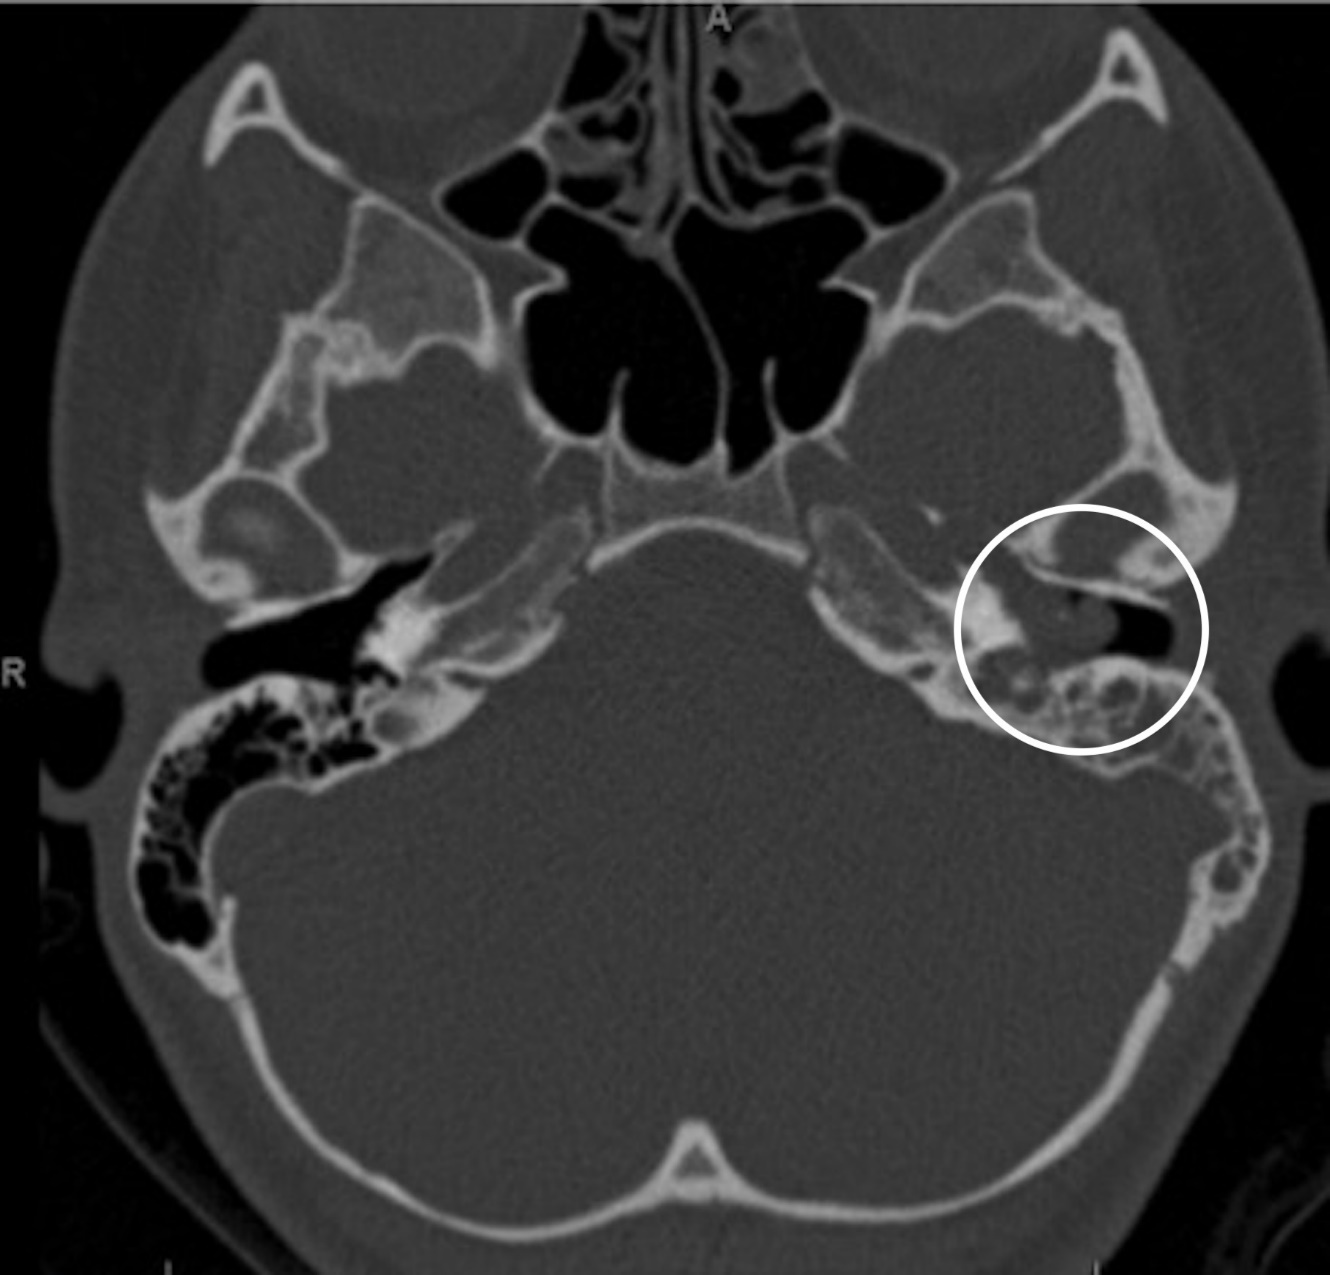

A CT scan of the temporal bones showed nonspecific, complete opacification of the middle ear and mastoid on the affected side. (Figure 2) An additional MRI scan was obtained showing an enhanced soft tissue mass centered within the left middle ear cavity. No intracranial involvement was noted.